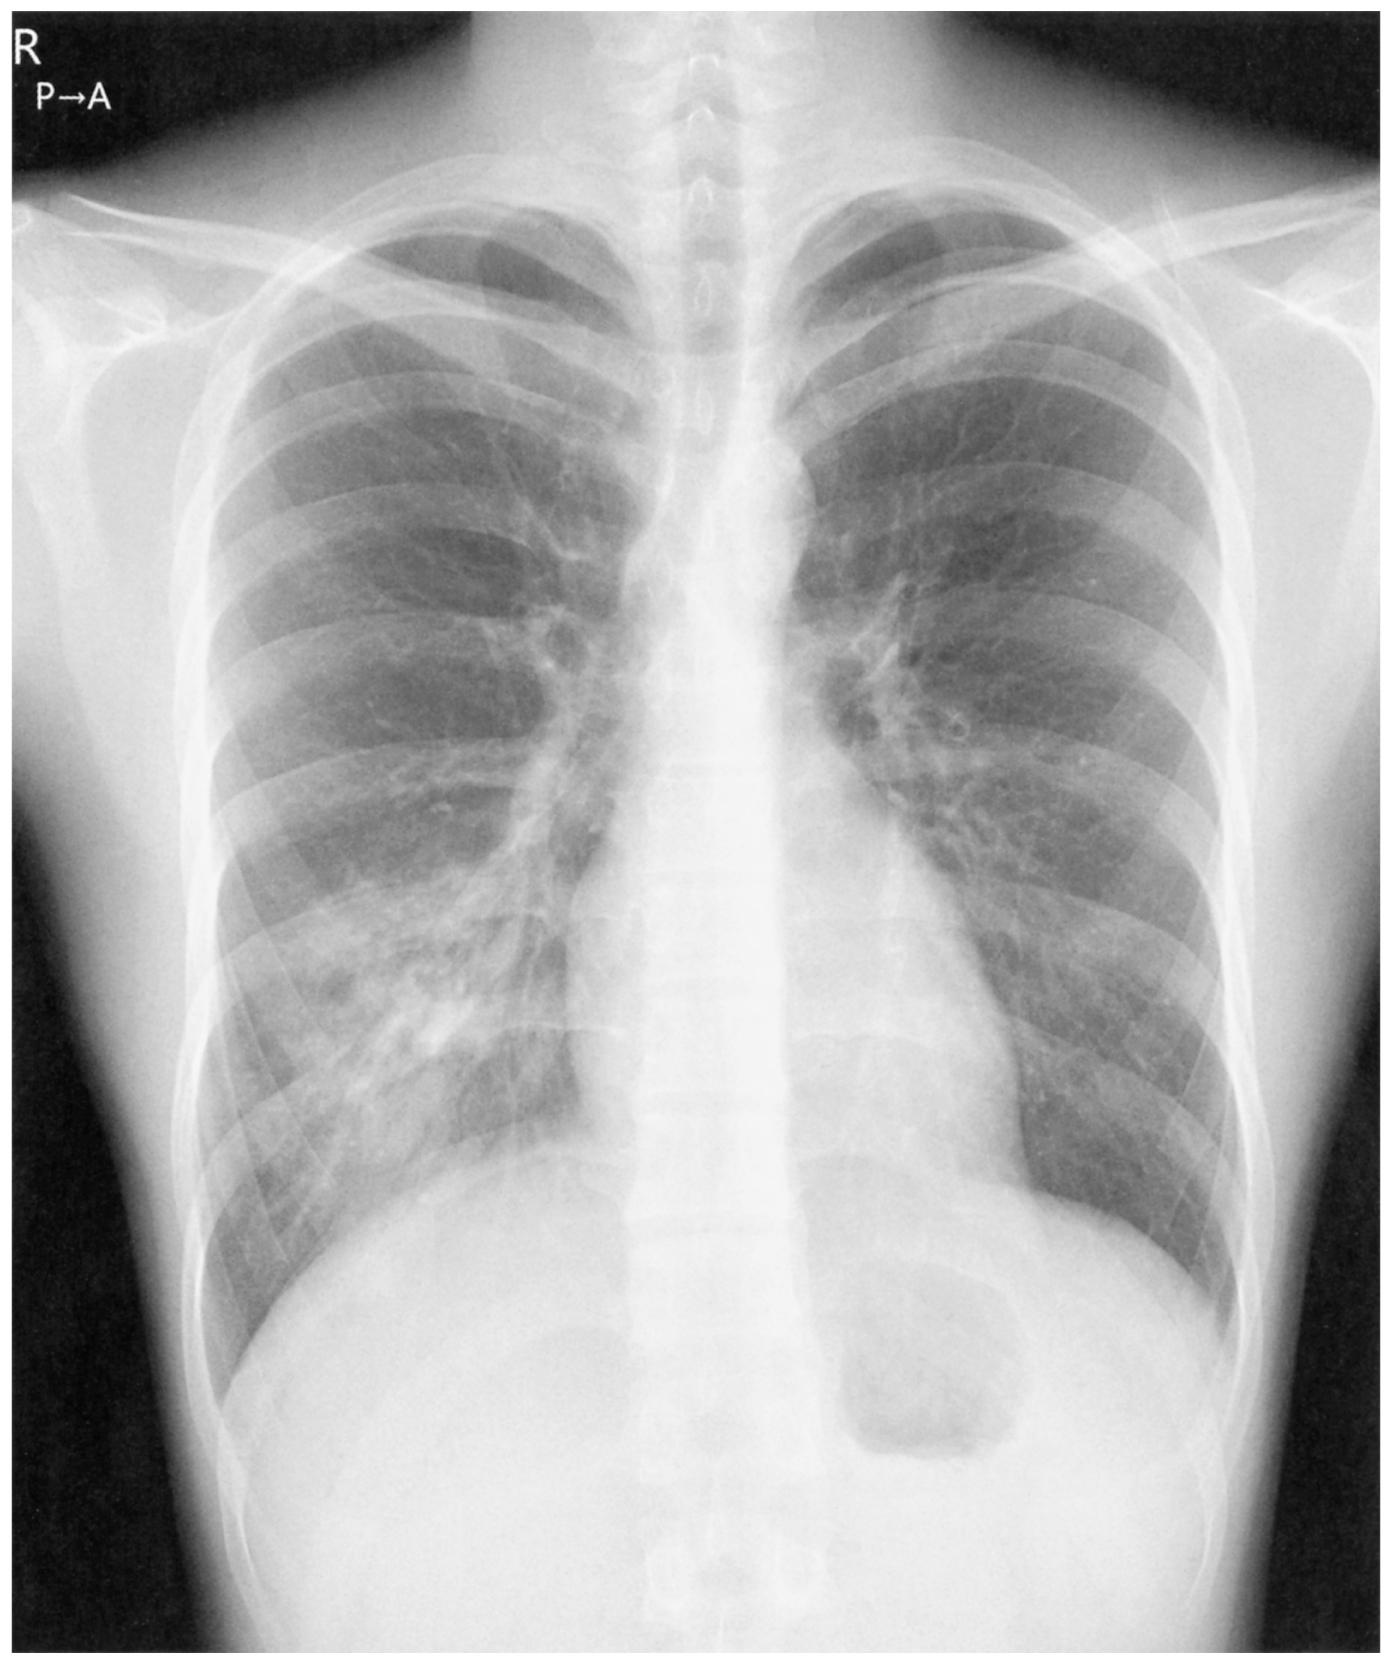

24歳の男性。3日前からの発熱と咳とを主訴に来院した。咳は乾性で頑固である。同様の症状を訴えている会社の同僚がいる。意識は清明。体温38.7℃。脈拍96/分,整。呼吸数20/分。呼吸音に異常を認めない。皮膚と口腔粘膜とに脱水所見は認めない。血液所見:白血球6,800(桿状核好中球9%,分葉核好中球55%,好酸球2%,単球6%,リンパ球28%)。CRP 7.8mg/dL。インフルエンザウイルス及び新型コロナウイルス〈SARS-CoV-2〉の抗原検査は陰性であった。誘発喀痰のGram染色や尿中抗原検査では原因菌は推定できなかった。胸部エックス線写真を下に示す。

無料会員登録していただくと、実際の解説をすべて見ることができます。急性の呼吸困難を主訴とする疾患としては,喉頭浮腫,気道異物,自然気胸,気管支喘息,慢性閉塞性肺疾患の急性増悪などの呼吸器疾患,心不全(急性,慢性の急性増悪),肺血栓塞栓症などの循環器疾患が代表的である。この症例では呼吸器感染症と心不全が疑われるが,胸部エックス線写真は肺炎像というよりも両心不全を示唆する所見を示している。診断:心不全(両心不全)(Nohria分類wet and warm) 選択肢考察 ×a 強い呼吸困難,胸痛などにより安静が保てない場合には,血管拡張による前負荷軽減と,交感神経抑制による心筋酸素消費量の減少を目的としてモルヒネを使用する。この症例ではモルヒネが必要となるほどの興奮状態ではない。